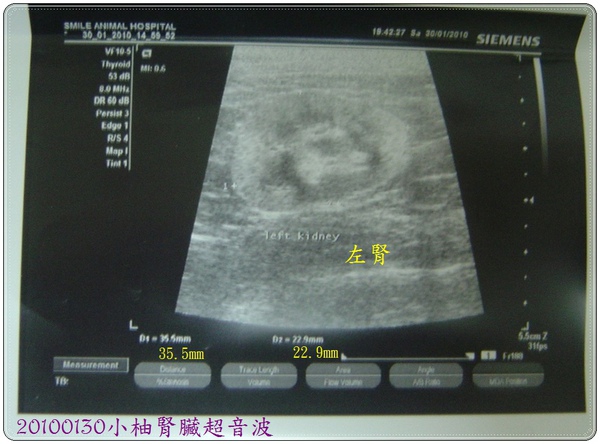

2.小柚腎臟超音波:

A.左腎:約35.5*22.9mm,施醫師認為並無前一個醫生所說的形狀不清楚的狀況,尺寸也正常,無萎縮,對此施醫師表示應為前一位醫生超音波沒照好,才會有左腎萎縮的結論產生。此外血流狀況正常,唯一要注意的是腎臟中有發現結晶。